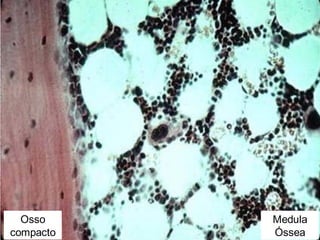

Medula óssea Osso compacto Músculo

Trabécula óssea

Medula óssea

Osso

compacto

Medula

Óssea

Medula óssea do indivíduo adulto